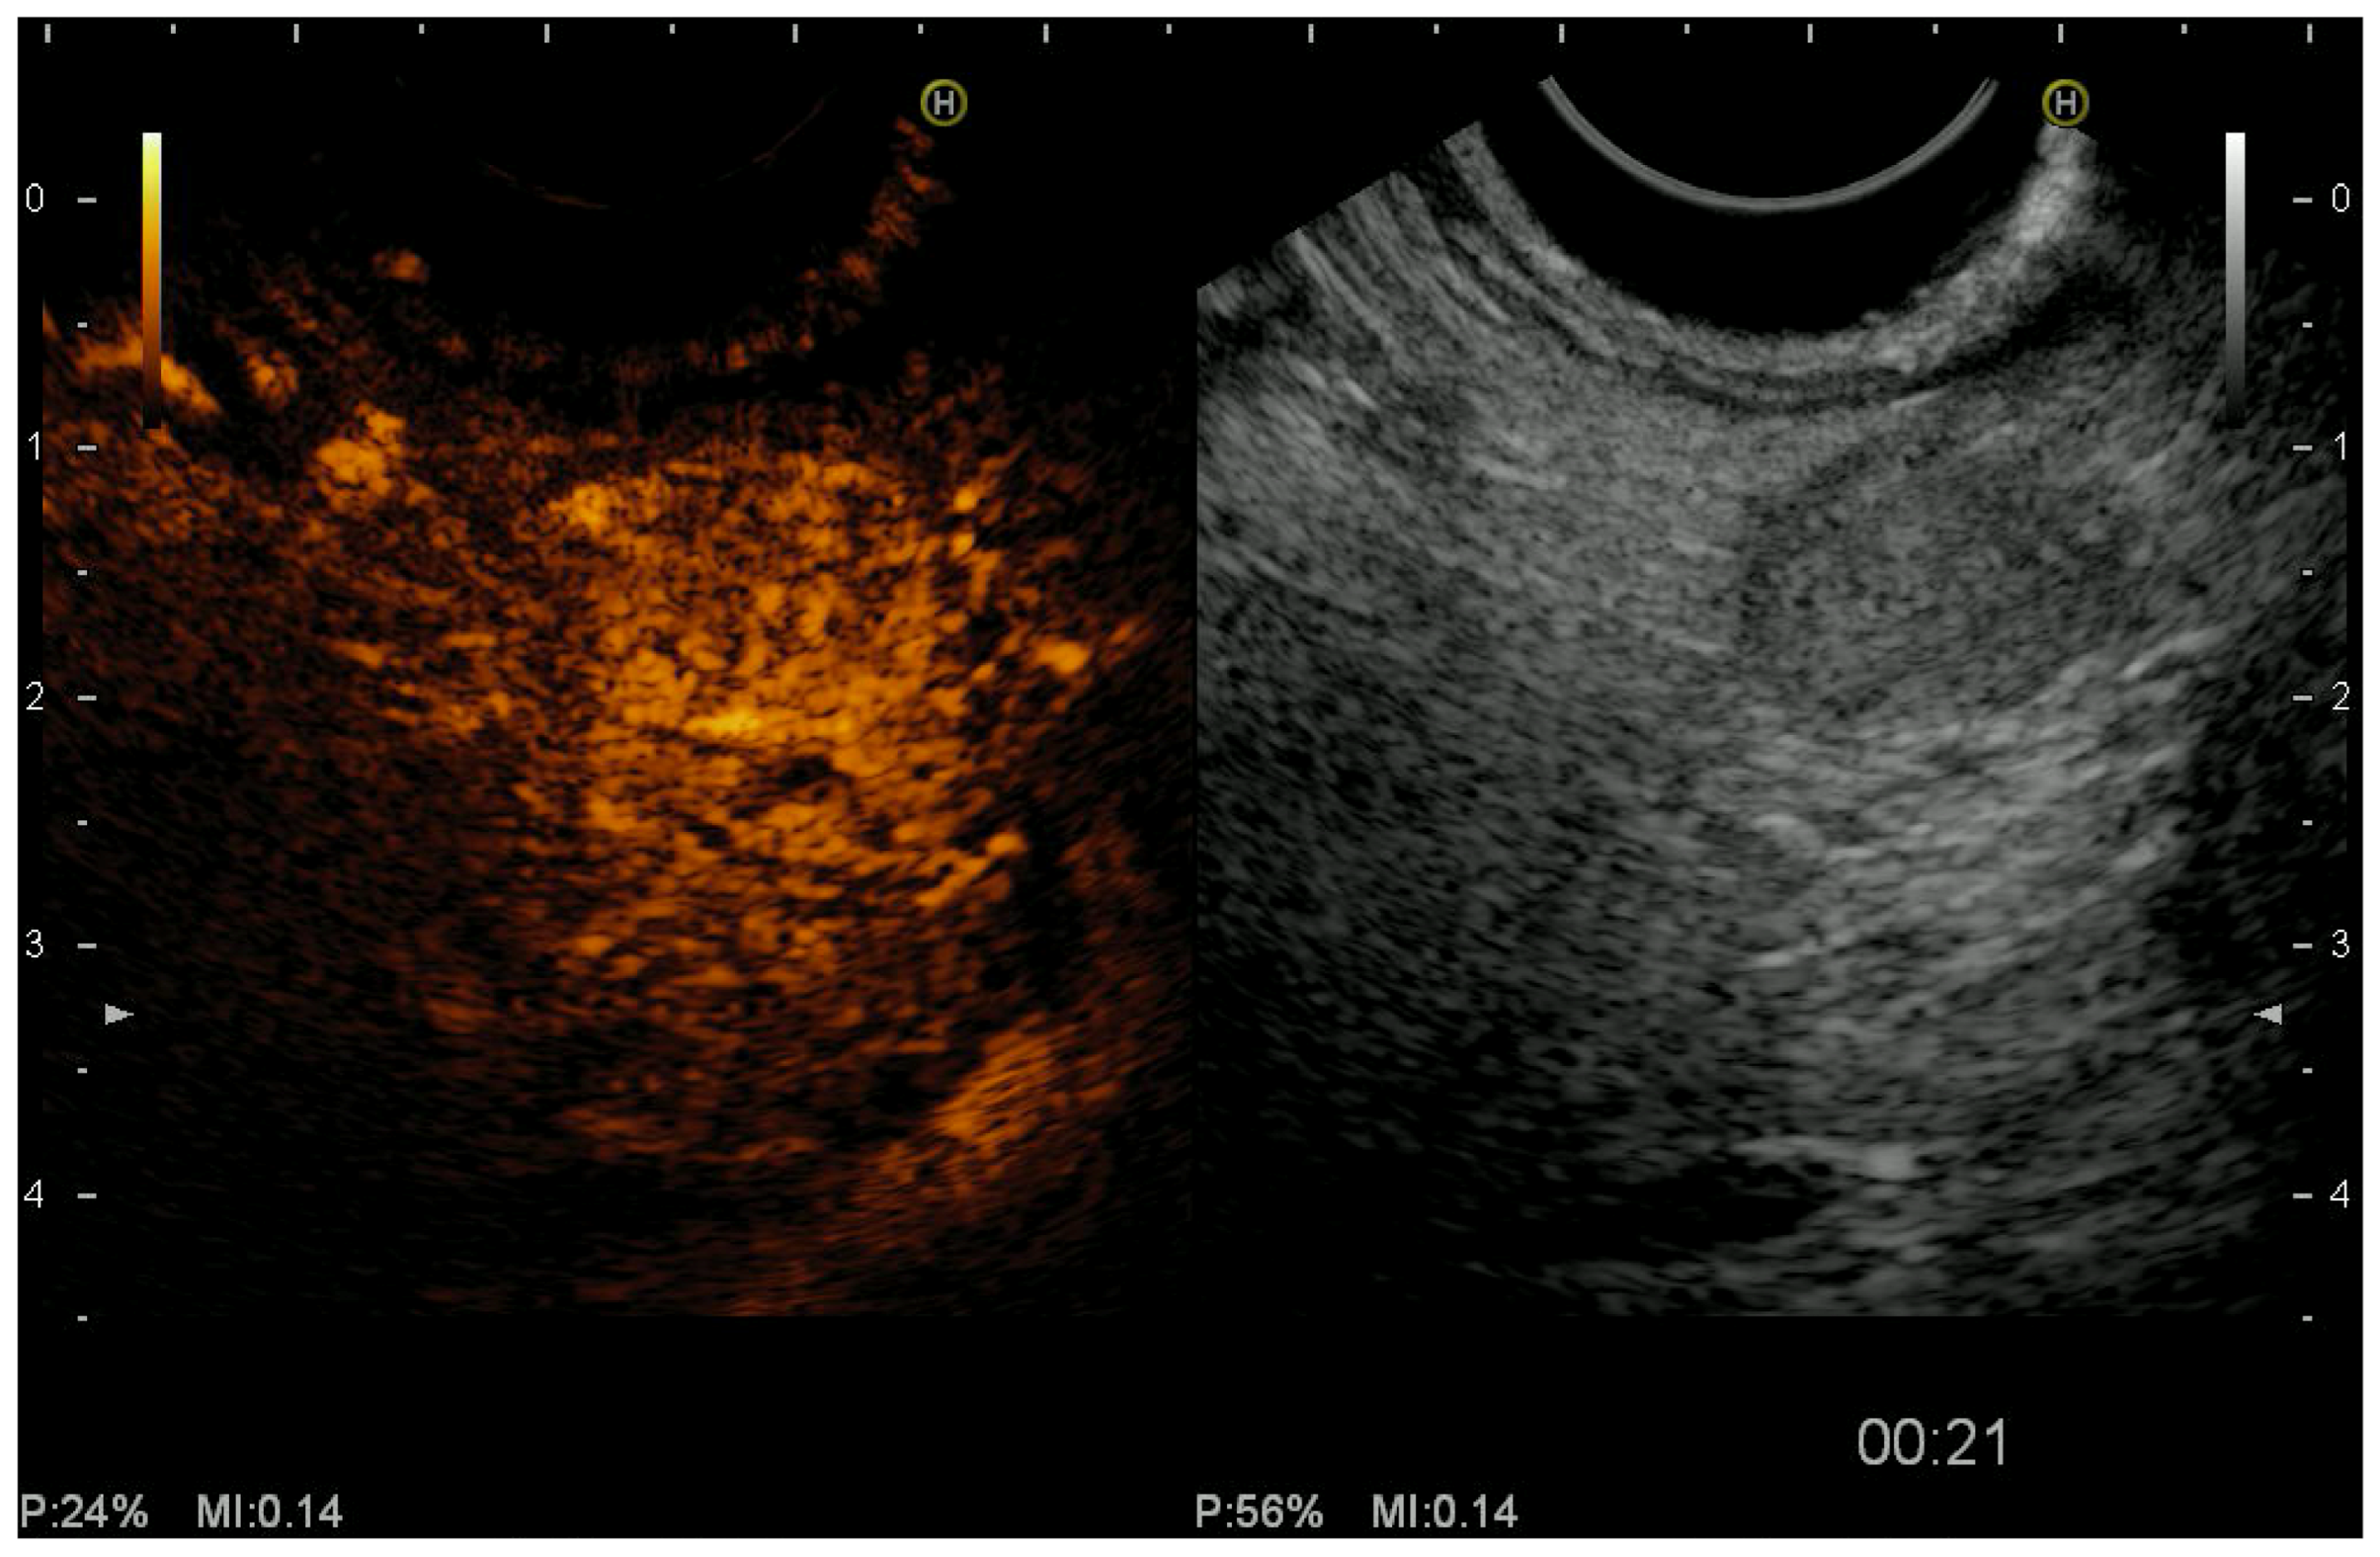

2.3. Color Doppler EUS and Contrast-Harmonic EUS (CH-EUS)

- Saftoiu, A.; Napoleon, B.; Arcidiacono, P.G.; Braden, B.; Burmeister, S.; Carrara, S.; Cui, X.W.; Fusaroli, P.; Gottschalk, U.; Hocke, M.; et al. Do we need contrast for EUS? Endosc. Ultrasound 2020, 9, 361–368. [Google Scholar] [CrossRef]

- Palazzo, M.; Napoléon, B.; Gincul, R.; Pioche, M.; Pujol, B.; Lefort, C.; Fumex, F.; Hautefeuille, V.; Fabre, M.; Cros, J.; et al. Contrast harmonic EUS for the prediction of pancreatic neuroendocrine tumor aggressiveness (with videos). Gastrointest. Endosc. 2018, 87, 1481–1488. [Google Scholar] [CrossRef]

- Kitano, M.; Kudo, M.; Yamao, K.; Takagi, T.; Sakamoto, H.; Komaki, T.; Kamata, K.; Imai, H.; Chiba, Y.; Okada, M.; et al. Characterization of Small Solid Tumors in the Pancreas: The Value of Contrast-Enhanced Harmonic Endoscopic Ultrasonography. Am. J. Gastroenterol. 2012, 107, 303–310. [Google Scholar] [CrossRef] [PubMed]

- Ishikawa, T.; Itoh, A.; Kawashima, H.; Ohno, E.; Matsubara, H.; Itoh, Y.; Nakamura, Y.; Nakamura, M.; Miyahara, R.; Hayashi, K.; et al. Usefulness of EUS combined with contrast-enhancement in the differential diagnosis of malignant versus benign and preoperative localization of pancreatic endocrine tumors. Gastrointest. Endosc. 2010, 71, 951–959. [Google Scholar] [CrossRef]